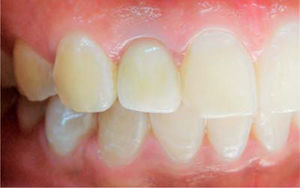

La restauración final fue atornillada con un torque de 15 Ncm (Figura 9). Veinticuatro meses después de la carga protésica, la mucosa periimplantar está en buenas condiciones.

DiscusiónBasados en la evidencia científica, los parámetros que influyen en el color de la mucosa periimplantar son el espesor del tejido y el material del pilar.14,15 Este reporte de caso evidencia el impacto de la modificación del color sobre la parte submucosa de un pilar en zirconio, logrando un resultado estético favorable.

Sin embargo, Bressan et al20 reportan que el pilar de zirconio blanco genera una decoloración leve en la mucosa delgada; para contrarrestar este efecto Buchi et al10 presentan la modificación de un pilar en zirconio aplicando cerámica rosada en la zona submucosa obteniendo excelente resultado. En este caso esta observación fue confirmada, por esto el pilar de zirconio en la zona blanca submucosa se enmascara con cerámica rosada, y en coronal, una cerámica fluorescente eliminando la apariencia grisácea por la translucidez gingival de la mucosa periimplantar. A su vez se compensa la alta translucidez de la cerámica rosada, conservando la luminosidad del tejido y el cambio de color de la mucosa con apariencia natural que satisface las necesidades del paciente.